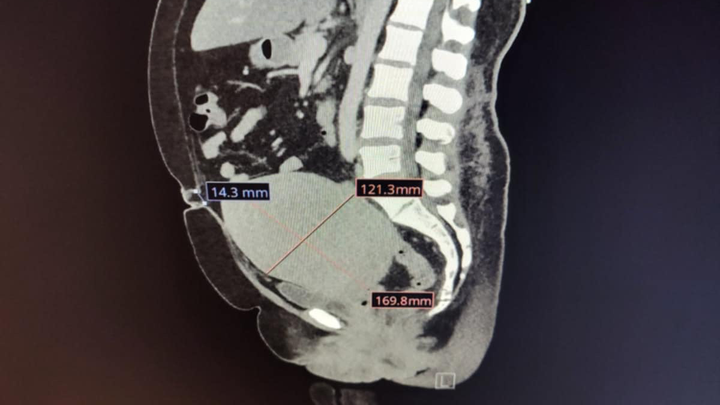

Hello everyone, my name is Melissa and I am in desperate need of a hysterectomy and an umbilical hernia repair surgery. I need to have both surgeries at the same time. My uterus is the size of a basketball and needs to be removed because it’s pressing against all my vital organs and main vein.